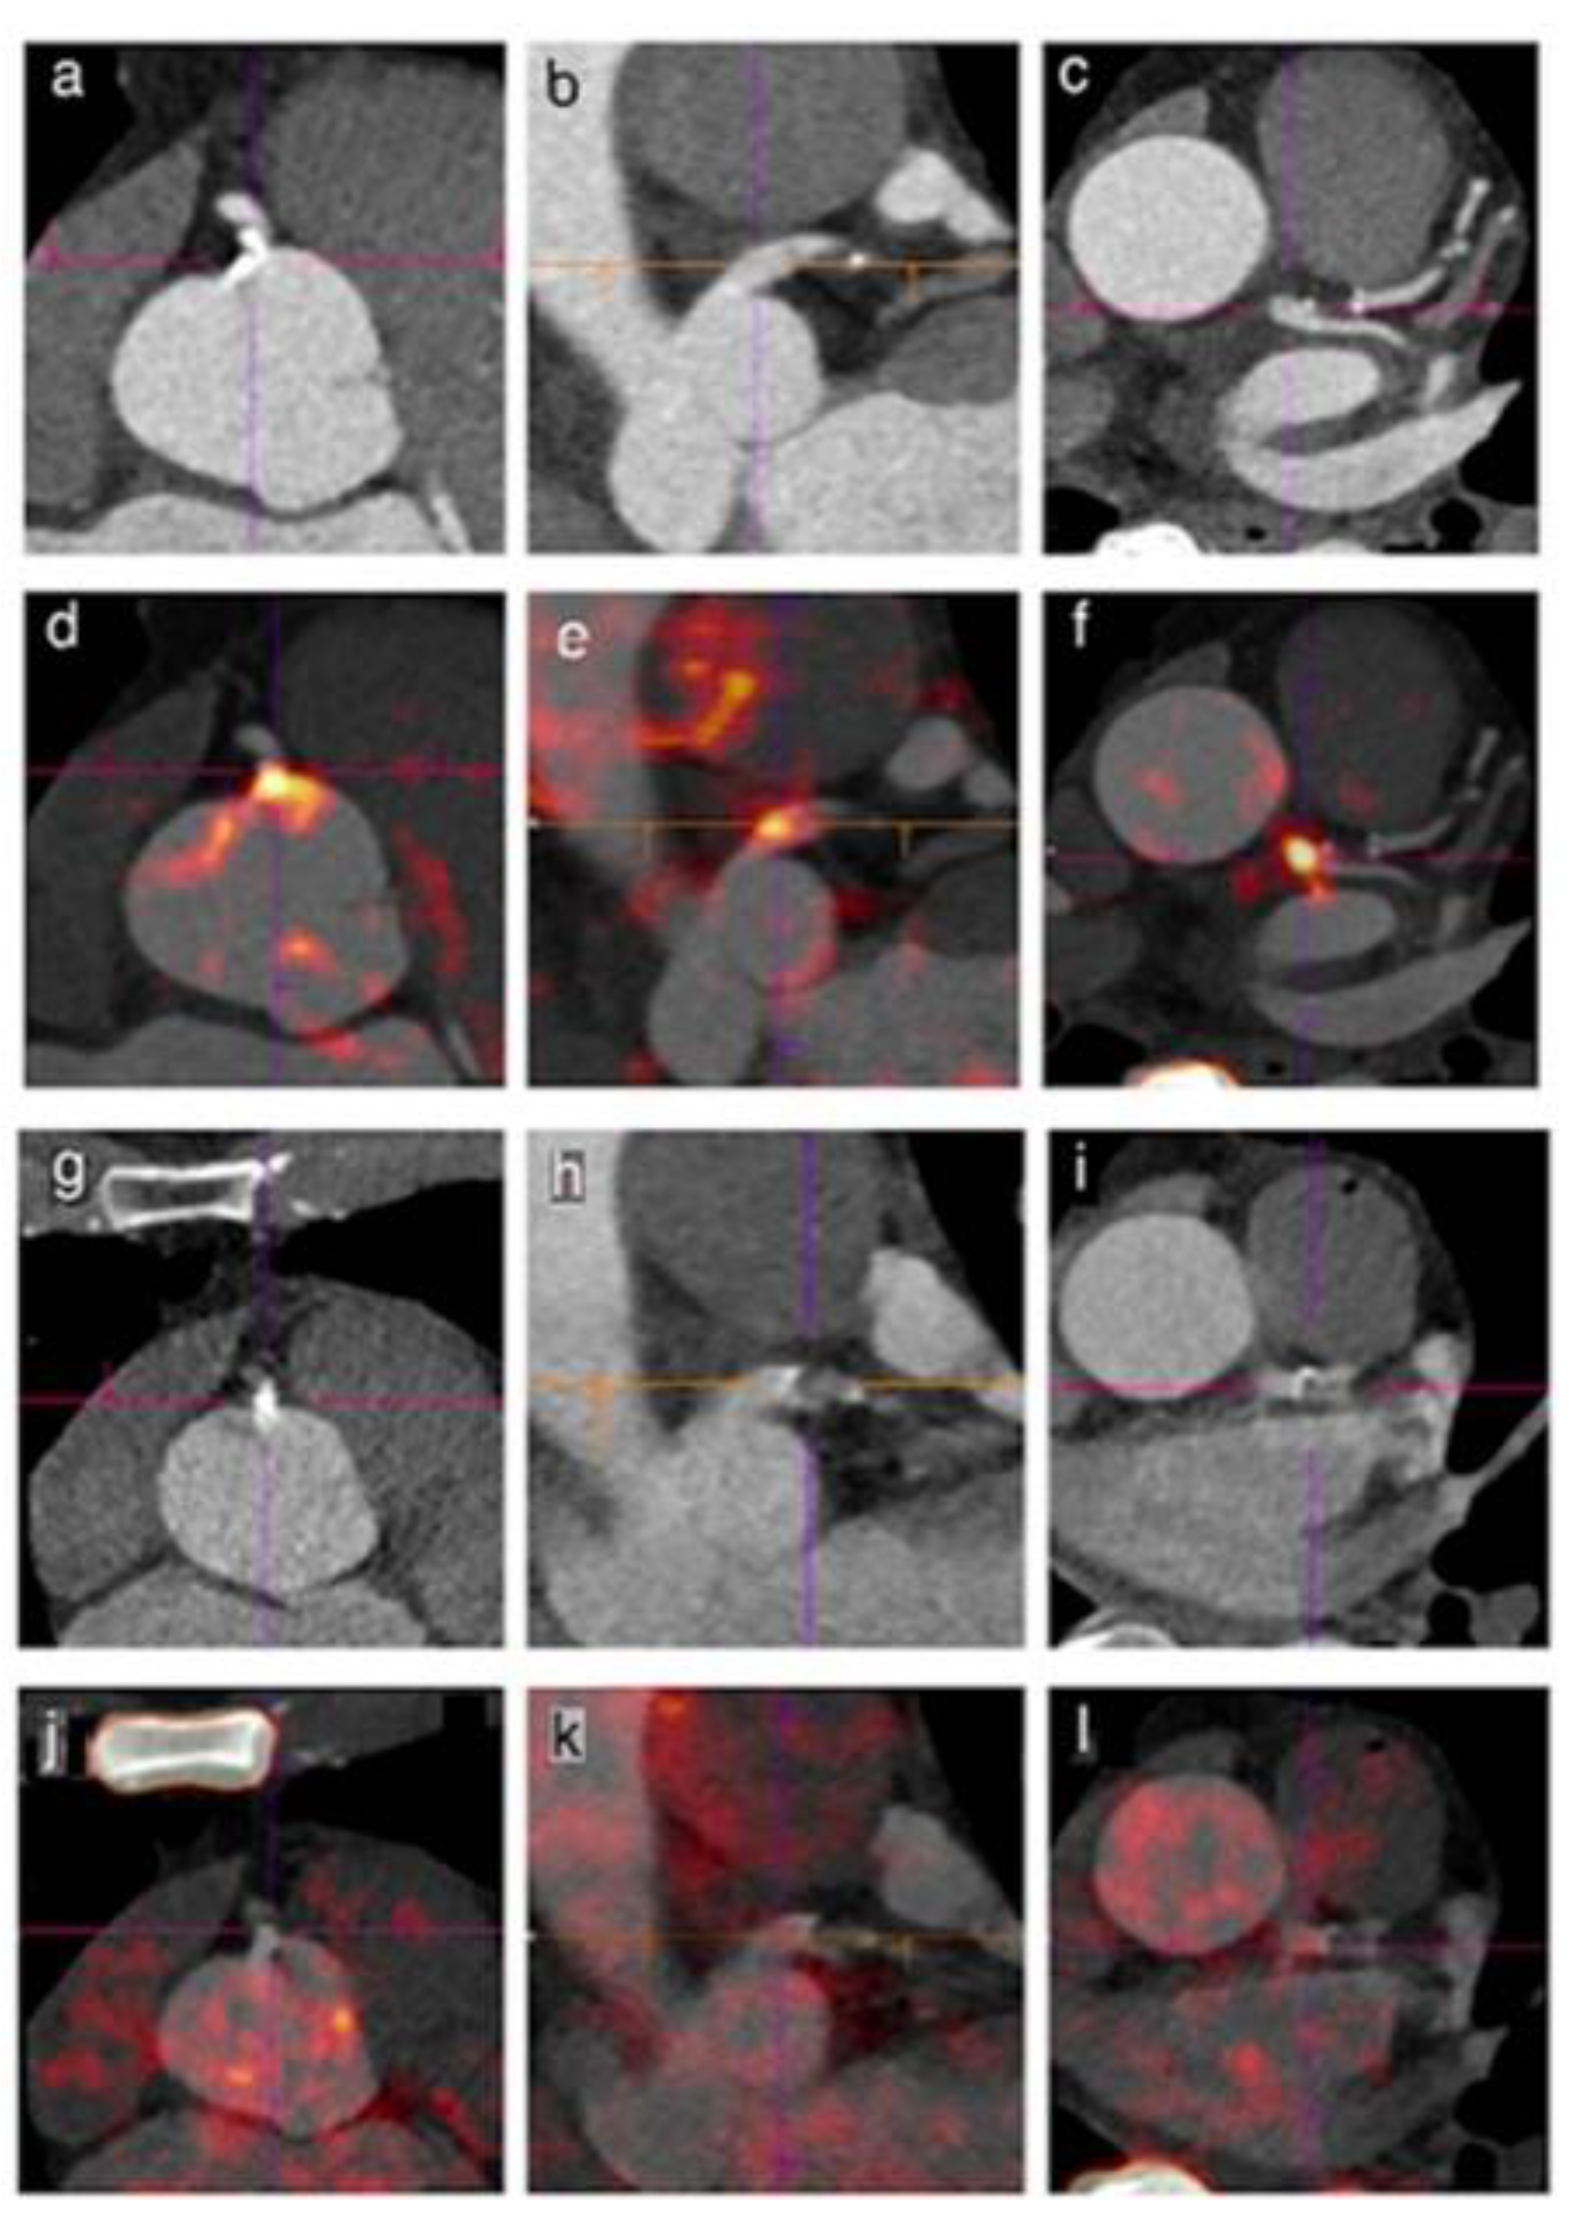

3.3. NaF Uptake in Vulnerable, High Risk and Ruptured Plaque

3.4. Association between NaF Uptake and Risk Factors